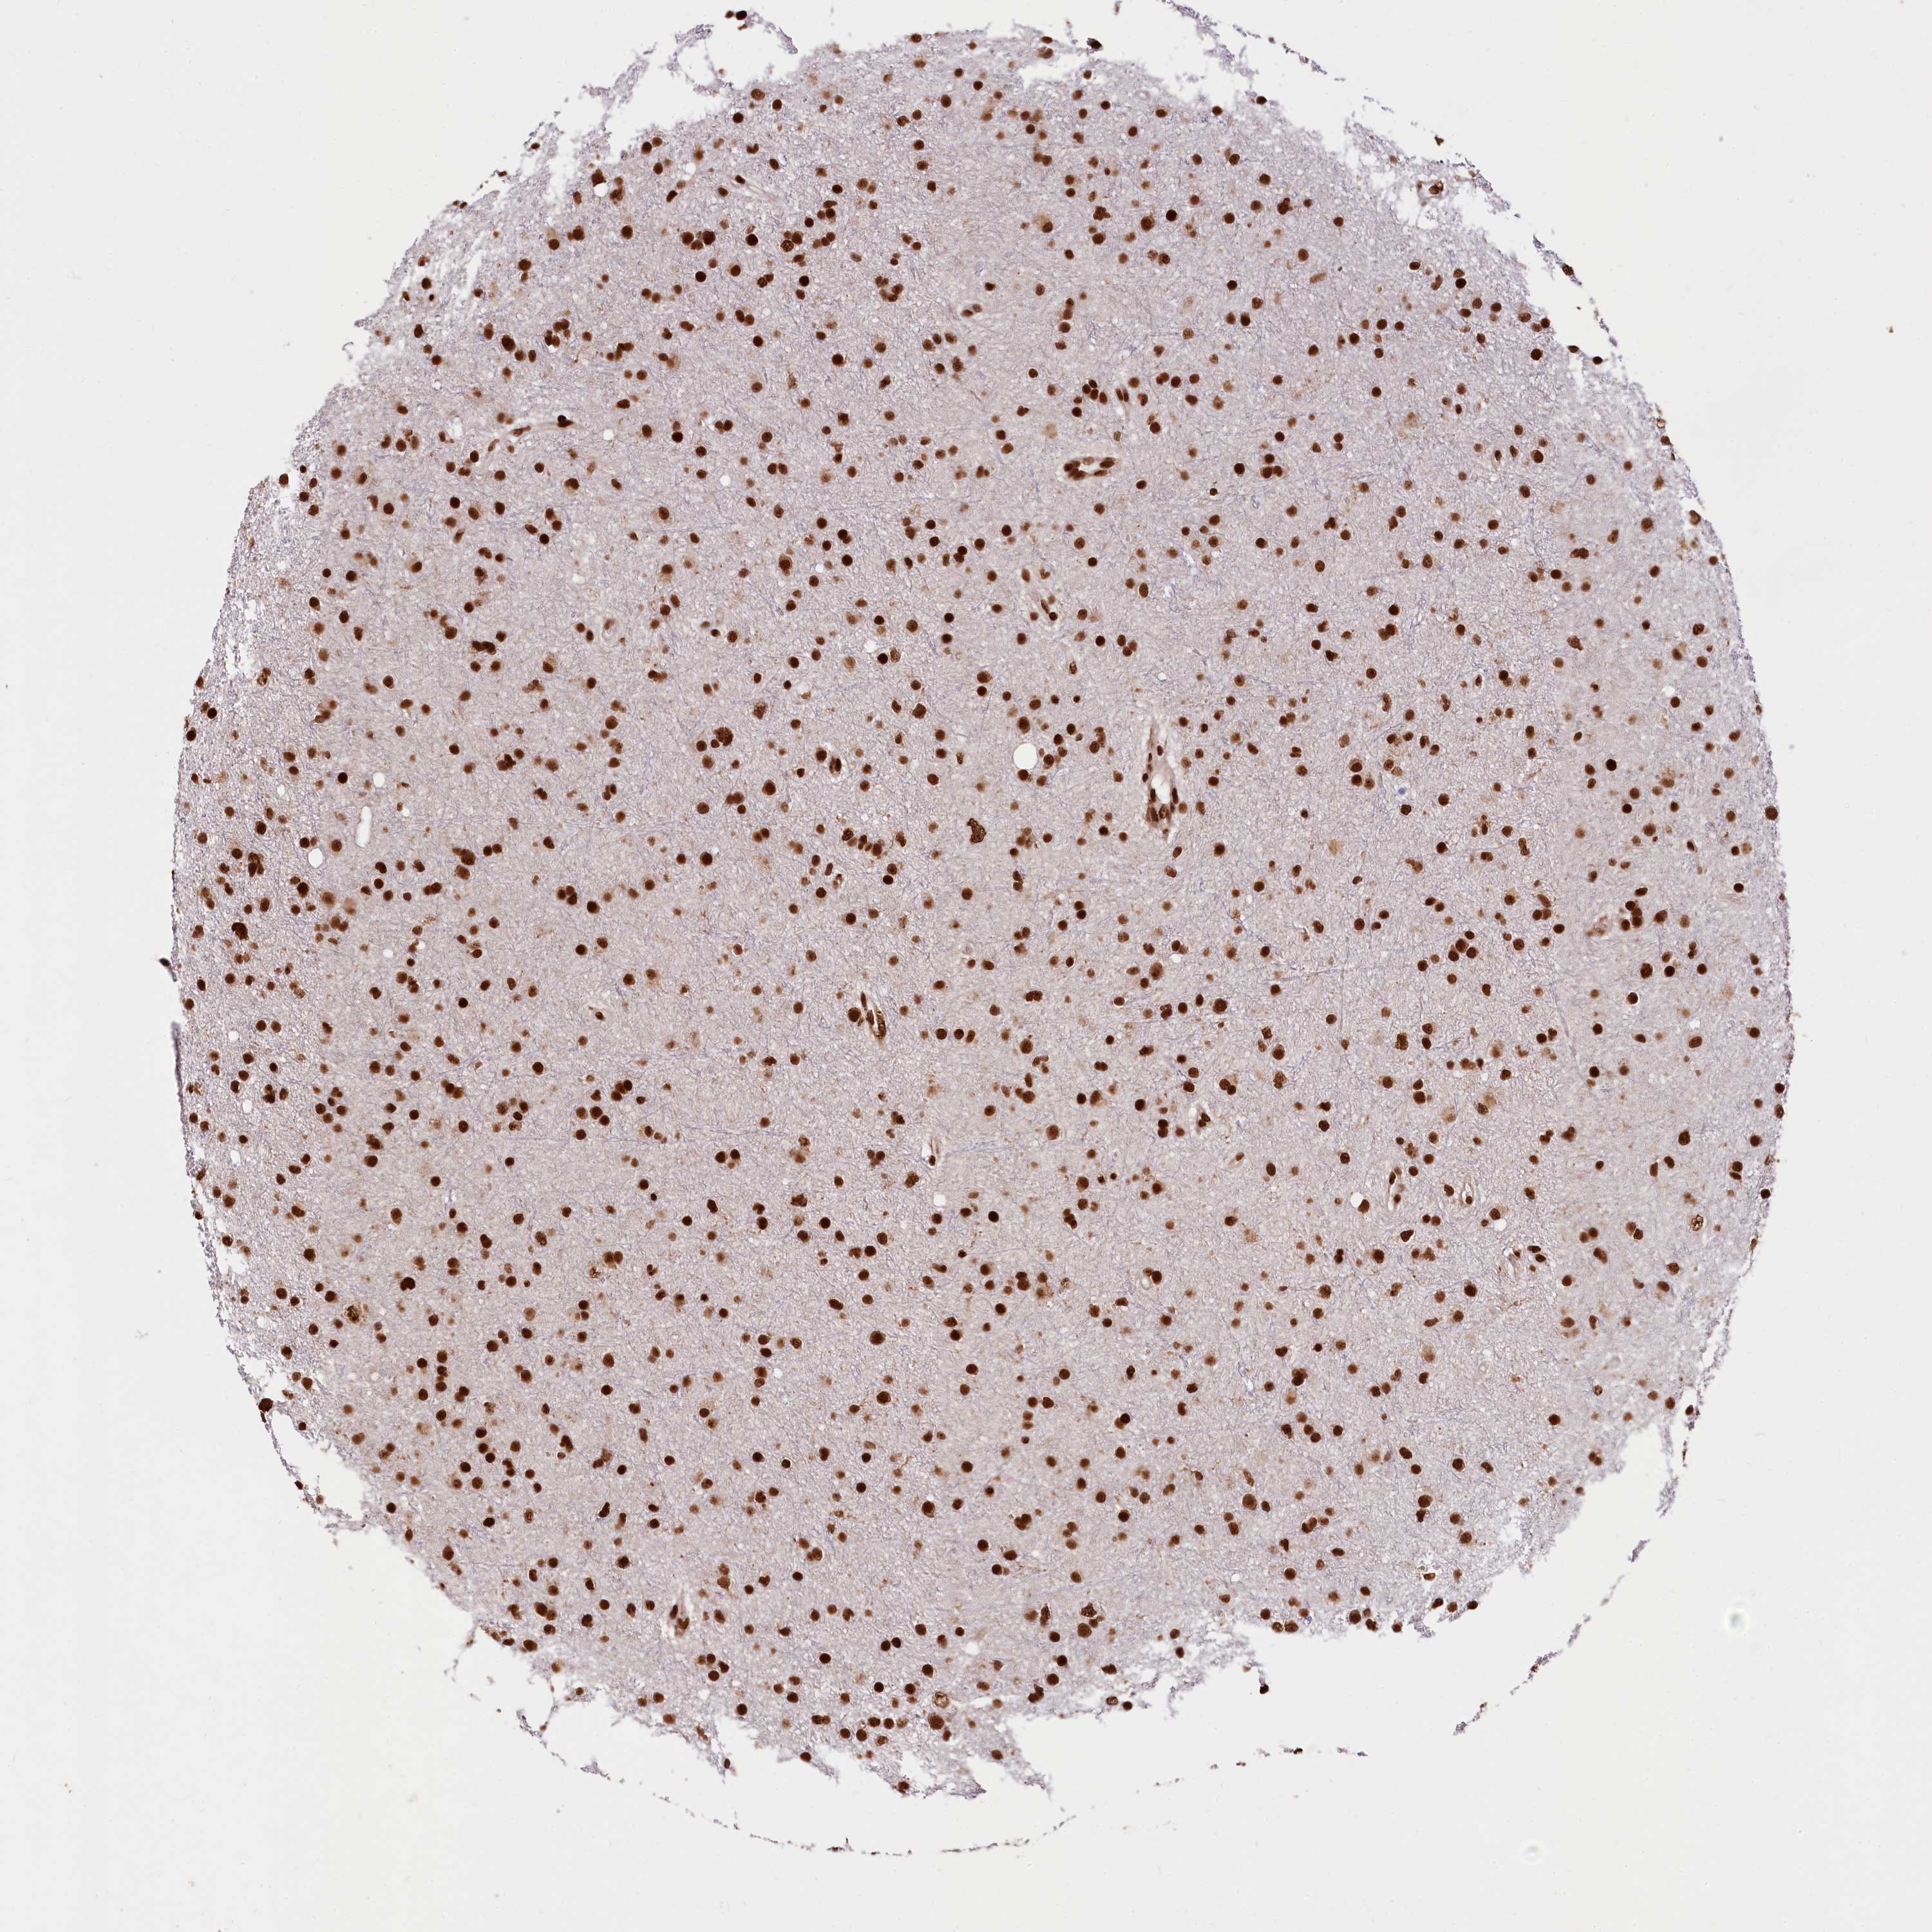

GLIOMA - Protein expressioni

A mouse-over function shows sample information and annotation data. Click on an image to view it in a full screen mode. Samples can be filtered based on level of antibody staining by selecting one or several of the following categories: high, medium, low and not detected. The assay and annotation is described here.

Note that samples used for immunohistochemistry by the Human Protein Atlas do not correspond to samples in the TCGA dataset.

Antibody stainingi

Antibody staining in the annotated cell types in the current human tissue is reported as not detected, low, medium, or high, based on conventional immunohistochemistry profiling in selected tissues. This score is based on the combination of the staining intensity and fraction of stained cells.

Each image is clickable and will lead to virtual microscopy that enables deeper exploration of all samples and also displays staining intensity scores, fraction scores and subcellular localization as well as patient and tissue information for each sample.

Antibody HPA039513

Antibody HPA040015

Staining

High

Medium

Low

Not detected

Intensity

Strong

Moderate

Weak

Negative

Quantity

>75%

75%-25%

<25%

None

Location

Nuclear

Cytoplasmic/membranous

Cytoplasmic/membranous,nuclear

Glioma, malignant, High grade

Glioma, malignant, Low grade